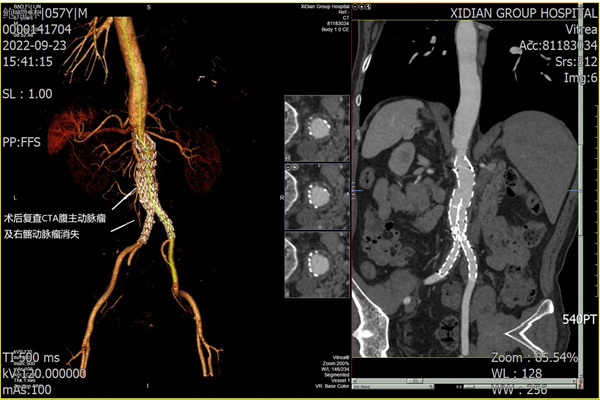

術(shù)后張叔恢復(fù)順利,未出現(xiàn)下肢缺血、截癱、 腸道缺血等并發(fā)癥。術(shù)后1周,復(fù)查腹主動(dòng)脈CTA,動(dòng)脈血流通暢,支架形態(tài)良好。

圖4:術(shù)后1周復(fù)查CTA